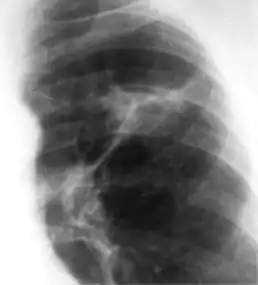

Ghon's complex is a lesion seen in the lung that is caused by tuberculosis.[1][2] The lesions consist of a Ghon focus along with pulmonary lymphadenopathy within a nearby pulmonary lymph node. A Ghon's complex retains viable bacteria, making them sources of long-term infection, which may reactivate and trigger secondary tuberculosis later in life.[3]

In countries where cow milk infected with Mycobacterium bovis has been eliminated (due to culling of infected cows and pasteurization), primary tuberculosis is usually caused by Mycobacterium tuberculosis and almost always begins in the lungs. Typically, the inhaled bacilli implant in the distal airspaces of the lower part of the upper lobe or the upper part of the lower lobe, usually close to the pleura. As sensitization develops, a 1 to 1.5 cm area of gray-white inflammation with consolidation emerges, known as the Ghon focus. In most cases, the center of this focus undergoes caseous necrosis. Tubercle bacilli, either free or within phagocytes, drain to the regional nodes, which also often caseate. This combination of parenchymal lung lesion and nodal involvement is referred to as the Ghon complex. During the first few weeks, there is also lymphatic and hematogenous dissemination to other parts of the body.

The Ghon complex undergoes progressive fibrosis, often followed by radiologically detectable calcification (Ranke complex), and despite seeding of other organs, no lesions develop. Although they are often confused, Ranke complex and Ghon complex are not synonymous. The Ranke complex is an evolution of the Ghon complex (resulting from further healing and calcification of the lesion).[4][5]